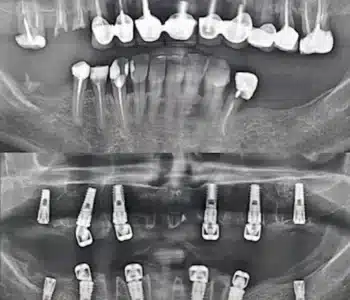

Dr. Seden Aksu is a specialist in modern implantology and surgical dentistry with extensive experience in the management of complex clinical cases. In her practice, she applies comprehensive surgical planning, minimally invasive techniques, and advanced regenerative technologies aimed at restoring both the function of the dentoalveolar system and the aesthetics of the smile. Dr. Aksu has significant experience in performing implant procedures, bone augmentation, and periodontal surgery, including the treatment of patients with severe bone loss. The primary goal of her work is to achieve stable, long-term outcomes in implant rehabilitation and the restoration of oral tissue health.